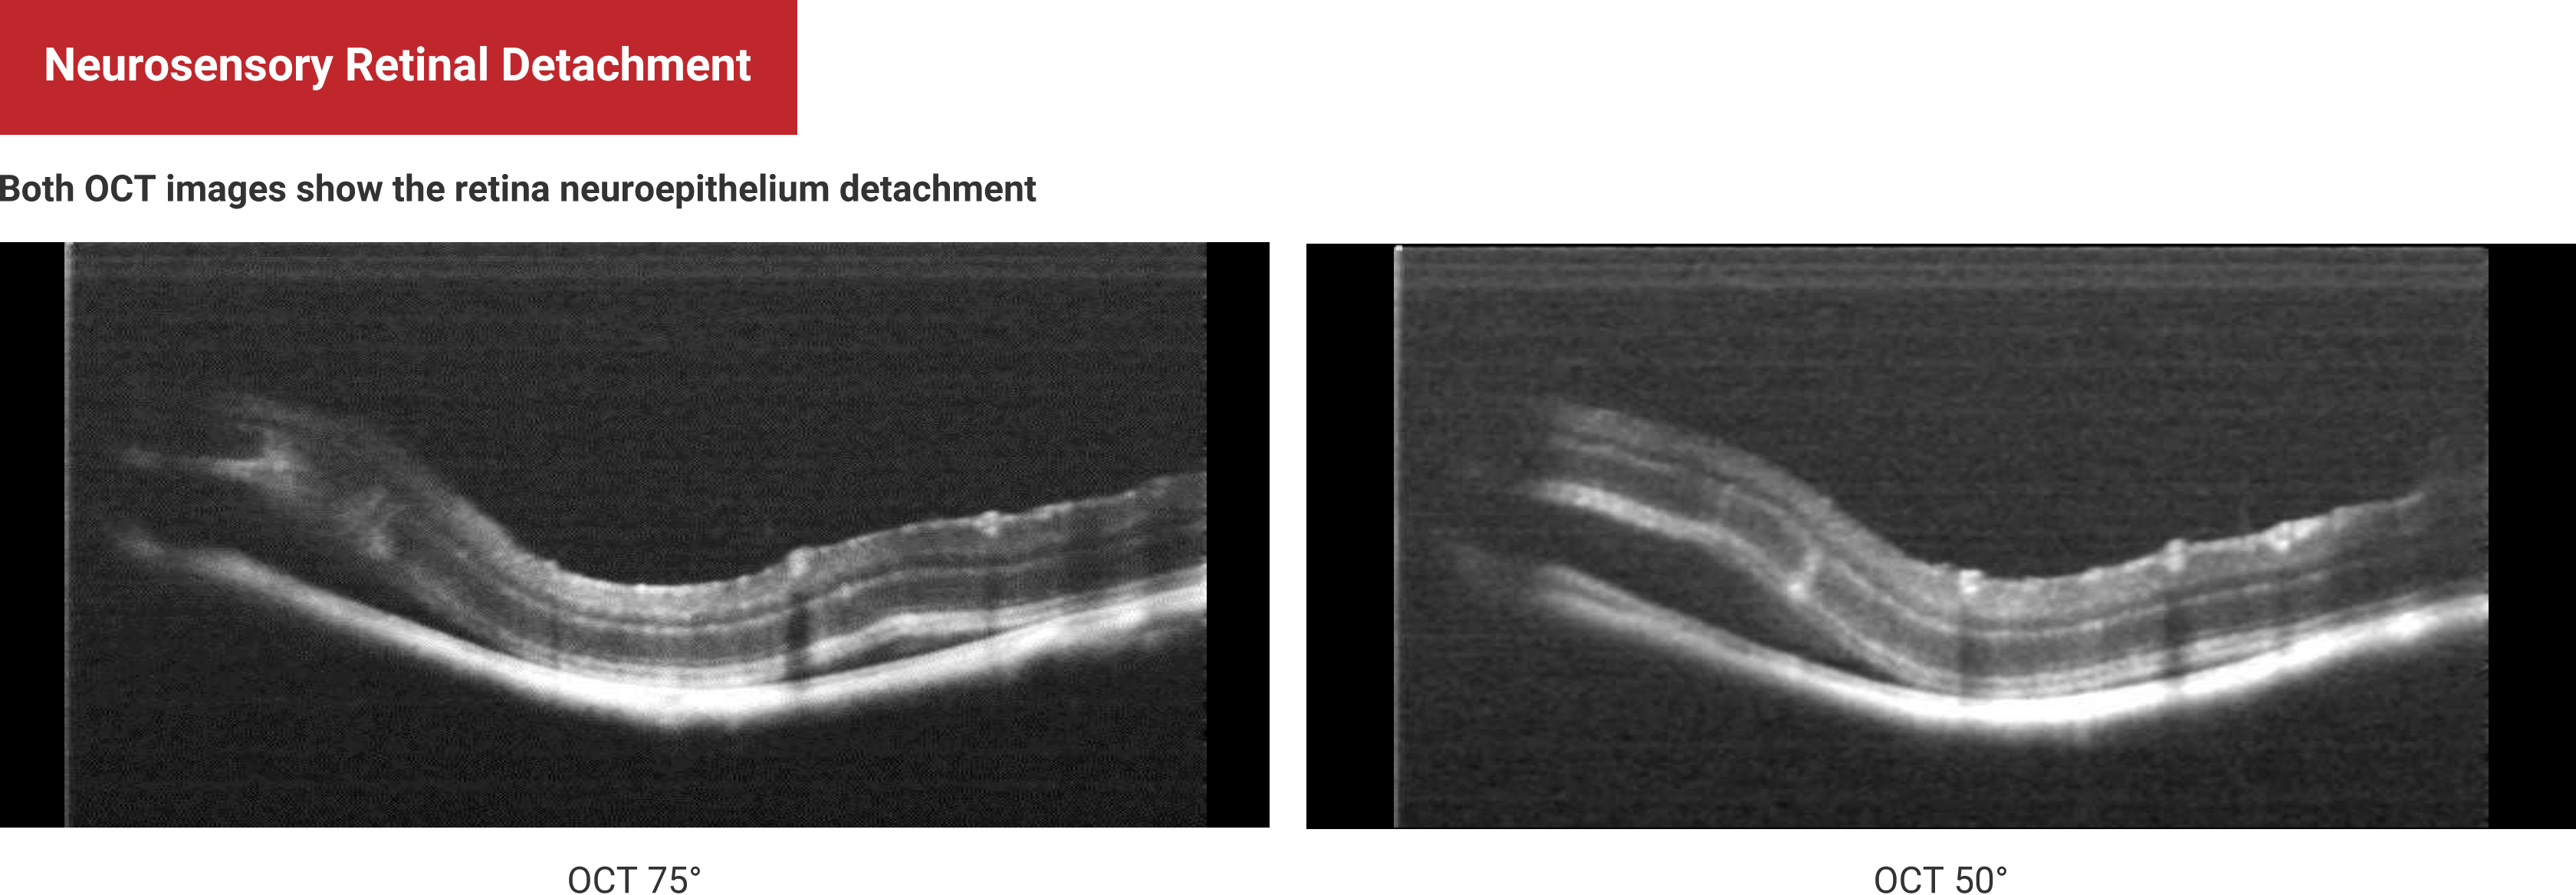

Multi-Modal Imaging

Neurosensory Retinal Detachment